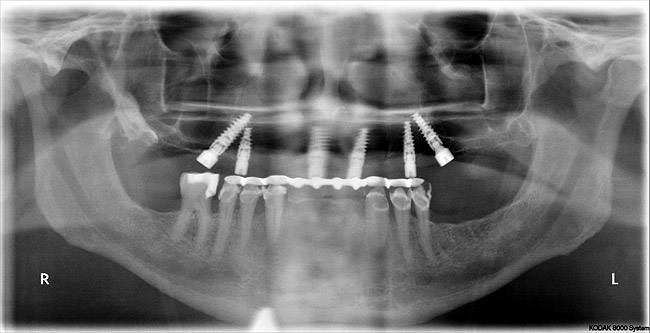

Figure 6  Postoperative panorex, “all-on-six” patient in Figure 5. Note proximity of angled posterior implants to anterior wall of maxillary sinuses. Surgery performed flaplessly.

Figure 6

Panoramic and periapical radiographs are 2-dimensional (2-D) representations of a patient’s 3-D anatomy. Differences in radiographic machines and techniques can lead to image distortion, such as elongation and shortening of anatomy. Accurate evaluation and measurement of the relationship between the mental nerve, inferior alveolar nerve (Figure 4), or nasopalatine/incisive nerve, and the planned implant position can best be determined and planned by a 3-D evaluation of the anatomy as related to the planned restoration.3,30 Implant placement in patients in whom there is a question of nerve or sinus proximity is most accurate using “virtual” treatment planning and placement using CT-generated guides, thus minimizing potential patient morbidity. Technologies such as “all-on-four,” which is designed to maximize the intra-arch spread of implant platforms while avoiding the mandibular nerve and maxillary sinus, are excellent indications for CT-guided implant surgery (Figure 5 and Figure 6).